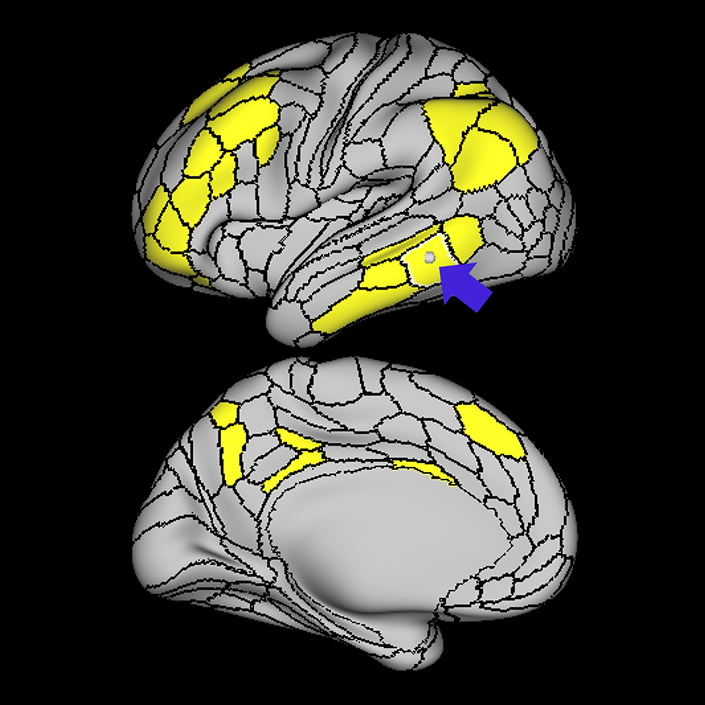

ᐅ SummaryArea 8C: part of the lateral frontal lobe regions. Within the context of spatial working memory, area 8C is involved in the interpretation of complex visual information and attention. Areas 8 and rostral 6, as part of the posterior dorsolateral frontal areas, are also involved in the maintenance of spatial information. ᐅ Where is it?Area 8C is located at the posterior part of the middle frontal gyrus. It is an anterior- to-posterior band which is lateral to area 8AV. ᐅ What are its borders?Area 8C has area 8AV as its main medial border. Its lateral border is with 3 inferior frontal sulcus areas: IFSp, IFJa, and IFJp. Area 55b and PEF (precentral eyefield) are its posterior borders (and discussed in a different section). Area p9-46v and to a lesser extent area 46 are its anterior neighbors. ᐅ What are its functional connections?Area 8C demonstrates functional connectivity to areas s6-8, i6-8, a9-46v, p9-46v, a10p, 8BL, 8AD, and 8AV in the dorsolateral frontal lobe, areas 8BM and d32 in the medial frontal lobe, areas IFSp, IFJp, a47r, p47r, and 44 in the inferior frontal lobe, area AVI in the insula, areas TE1m, TE1p, TE2a, STSva, and STSvp in the temporal lobe, areas IP1, IP2, LIPd, PFm, PGi and PGs in the inferior parietal lobe, and areas 7pm, 31pv, 31a, POS2, 23d, and d23ab in the medial parietal lobe. ᐅ What are its white matter connections?Area 8C is structurally connected to the arcuate/SLF and the contralateral hemisphere. Contralateral connections travel through the corpus callosum to end at 8C. Connections with the arcuate/SLF project posteriorly and wrap around the sylvian fissure to the posterior temporal lobe to end at PH and PHT. ᐅ What is known about its function?Within the context of spatial working memory, area 8C is involved in the interpretation of complex visual information and attention. Areas 8 and rostral 6, as part of the posterior dorsolateral frontal areas, are also involved in the maintenance of spatial information. |

A: lateral-medial

B: anterior-posterior

C: superior-inferior

DTI image |